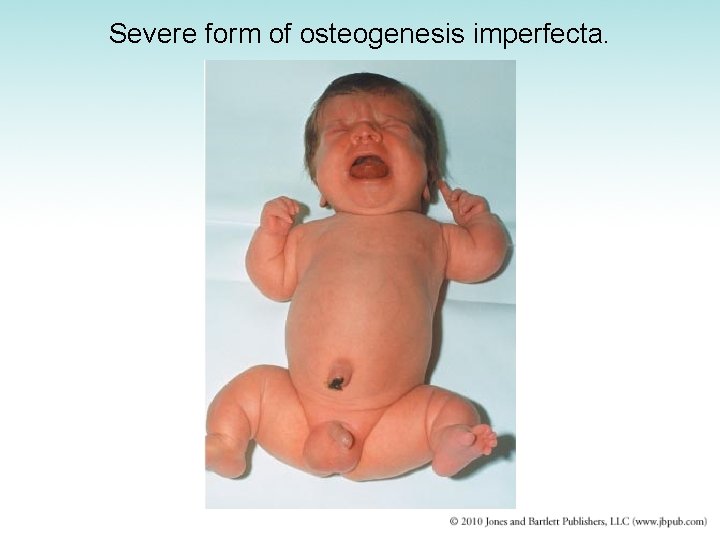

Congenital Malformations (1 of 2) • Achondroplasia – Faulty endochondral bone formation – Impaired growth of extremities and formation of skull bones – Causes dwarfism with disproportionately short limbs • Osteogenesis imperfecta – – – Thin and delicate bones easily broken May be born with multiple fractures Malformation of fingers and toes Extra digits or polydactyly Easily removed Fused digits more difficult to correct

Severe form of osteogenesis imperfecta.